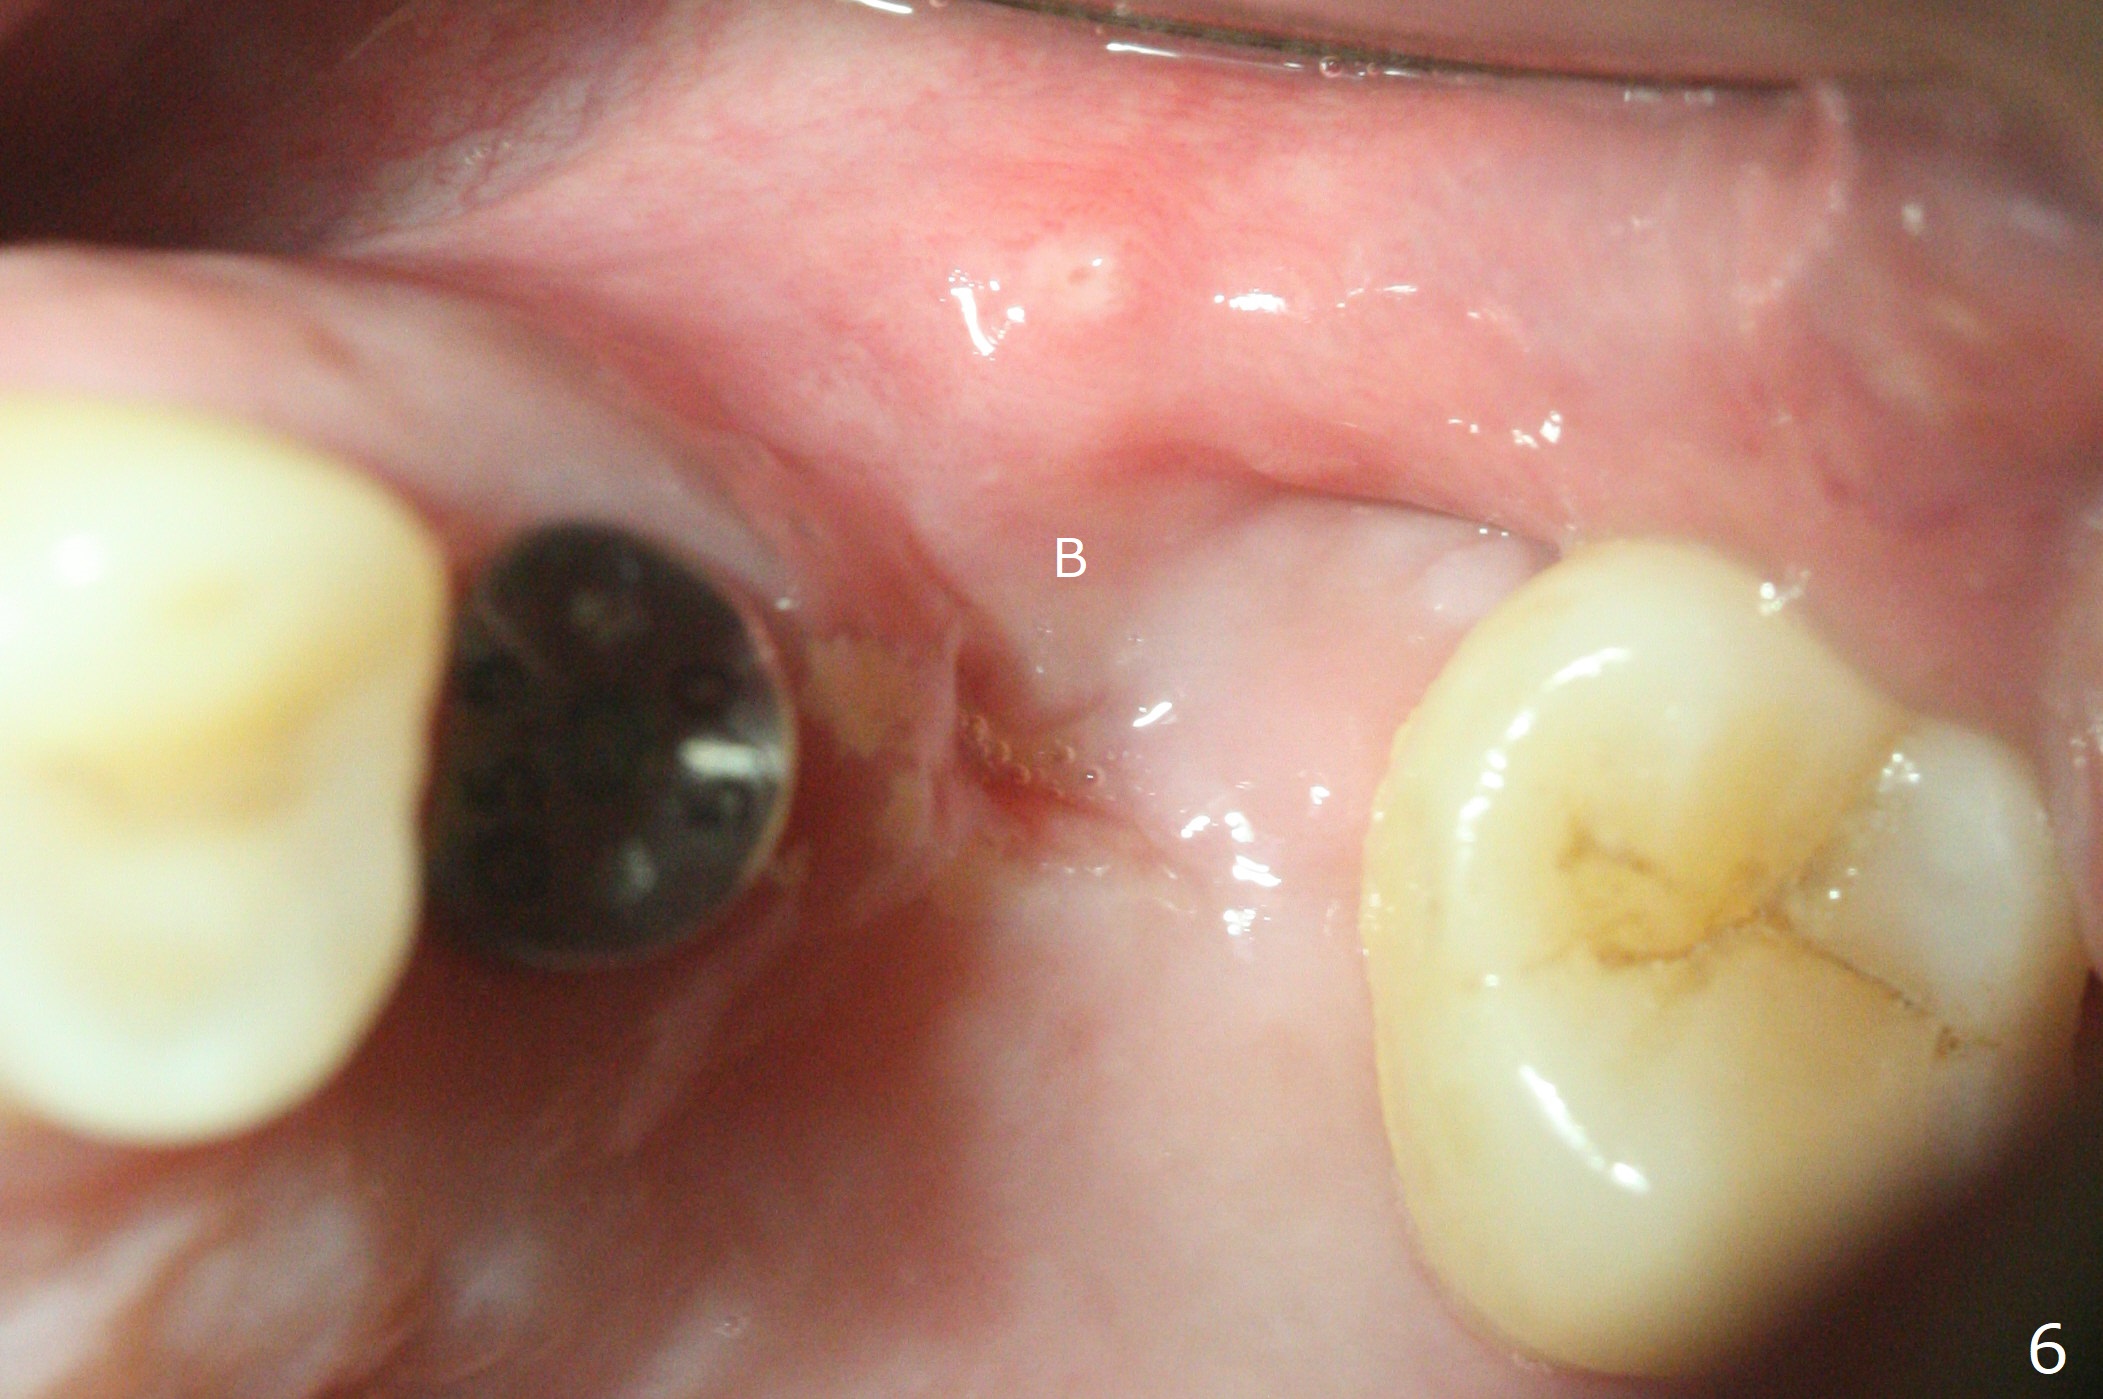

Fixture mount does not fit at #13 as an anchor. After 3.5x7.3 mm drill with 10.5 mm offset at #14, sinus lift drills (3.6x18 and 19 mm) are used. The sinus floor is intact. A 9 mm offset should be used. Following 4.0x10 mm dummy implant is placed for ~ 8.5 mm, the sinus floor is perforated while the sinus membrane is intact. After water lift, PRF membrane and allograft are inserted and pushed upward with the 4.0x10 mm dummy implant for ~ 10 mm (Fig.1). One more piece of PRF membrane and bone graft are lifted with a 4.5x10 mm dummy implant. A small dose of bone graft is elevated with a definitive implant (Fig.2,3, 5x10 mm). Is there enough bone to cover the apical part of the implant when the latter heals? When the patient returns for restoration 4.5 months postop, local oral hygiene is not good with light gingival erythema. There is tenderness when the healing abutment is being removed. It appears that osteointegraton is to occur; the mesial bone density is low (Fig.4 *). Healing abutment should be not placed when sinus lift repeatedly fails. In fact the implant is removed with the healing abutment 6.5 months postop. The buccal plate is missing, while the sinus floor is intact. Ossogen is placed, covered by Osteogen plug and sutured with PGA (Fig.5). The buccal plate remains concave 8 days postop (Fig.6 B). In the 4th trial, incision will be made, flaps dissected extensively with suture fixation. The existing guide is used to start osteotomy with point drill, followed by bone expansion. Reload the guide to place a narrower implant 4 or 4.5 mm with cover screw, and place sticky bone buccal. The latter is covered with PRF and suture. If stability is insufficient, perforate the sinus floor. Place a cemented abutment at #13 to hold periodontal dressing. Use profile drill if needed.Return to Upper Molar Immediate Implant, Trajectory II Xin Wei, DDS, PhD, MS 1st edition 08/13/2019, last revision 02/13/2021